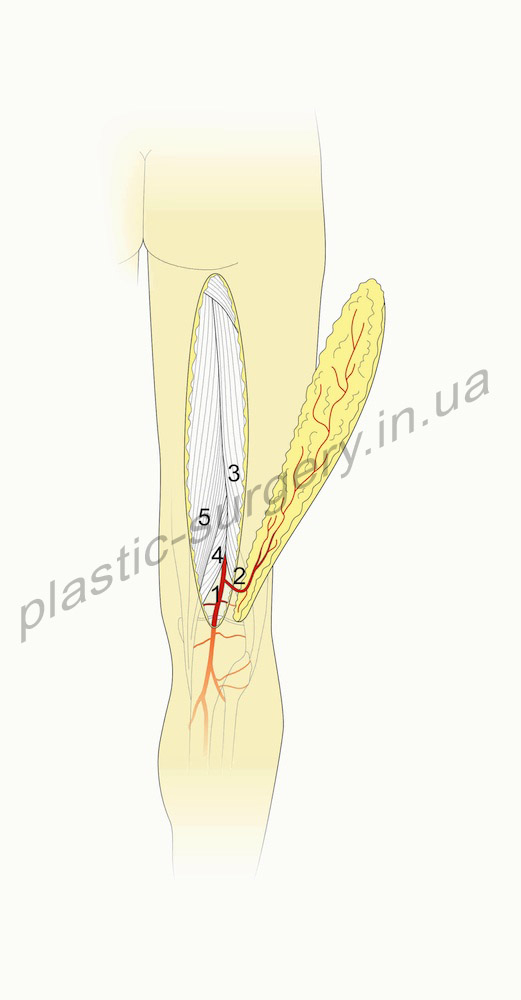

Рис. 2. Схематическое изображение. Задний лоскут бедра на третьем перфоранте глубокой артерии бедра (Third Perforator of the Profunda Femoris Artery Perforator (PFAP-3) Flap) (справа). 1- глубокая артерия бедра, 2- третий перфорант глубокой артерии бедра, 3- кожный перфорант, 4- двуглавая мышца бедра, 5- полусухожильная мышца (справа).

Задний лоскут бедра на третьем перфоранте глубокой артерии бедра (Third Perforator of the Profunda Femoris Artery Perforator (PFAP-3) Flap). PFAP-3 лоскут был изначально описан как задний лоскут бедра Song et al. [18], который продемонстрировал его использование в двух клинических случаях. Важно различать этот лоскут от PFAP лоскута (латеральный лоскут бедра). PFAP лоскут базируется на том же сосуде, который дает латеральную ветвь, перфорирующую латеральную межмышечную перегородку. В отличие от этого, PFAP-3 (задний бедренный) лоскут, базируется на задней ветви, которая идет медиально в срединном направлении задней поверхности бедра (рис.2). Задняя ветвь присутствует в 86% случаев. Это самая крупная из всех ветвей отходящих от первого, второго, или третьего перфорантов глубокой артерии бедра, которая следует в срединном направлении бедра. Кожный перфорант, который дает питание PFAP-3 лоскуту локализуется приблизительно на 2/3 расстояния между бугристостью сидалищной кости и средней точкой между мыщелками большеберцовой кости. Эта линия также определяет среднюю ось лоскута. Размеры кожного лоскута могут быть от бедренно-ягодичной складки до нижнего края подколенной ямки. Перфоратор, питающий этот лоскут, выходит в промежутке между двуглавой мышцей бедра и полусухожильной мышцами.

Сосудистая анатомия. Третий перфорант глубокой артерии бедра выходит ниже короткой приводящей мышцы бедра, и ниже сухожилия длинной приводящей мышцы бедра. Этот сосуд проходит кзади через длинную приводящую мышцу и короткую головку двуглавой мышцы бедра, и затем отдает ветви к широкой наружной мышце бедра (vastus lateralis m.). Третий перфорант глубокой артерии бедра в итоге дает ветвь, которая идет вдоль латеральной межмышечной перегородки и питает кожу латеральной поверхности бедра и латеральный лоскут бедра, и задне-латеральные мышцы бедра. Далее эта ветвь кровоснабжает двуглавую мышцу бедра, она также перфорирует глубокую фасцию и питает кожу центральной части задней поверхности бедра и является источником питания для PFAP-3 лоскута. Длина этой сосудистой ножки лоскута колеблятся от 5 см. до 10,7 см. А диаметр этой артерии колеблется от 1,5 до 2 мм. Сопровождающая вена имеет сходный размер.

Выделение лоскута. Поднятие лоскута начинается после идентификации необходимого кожного перфоранта с помощью допплеровского исследования. Лоскут выкраивается по переферии и поднимается над глубокой фасцией до уровня, где определяется отхождение от перфоранта мелких сосудов. В этом месте приходится рассечь фасциальные «манжеты», количество которых вариабельно, что позволяет проводить дальнейшую диссекцию сосудистой ножки в промежутке между двуглавой полусухожильной мышцами. Диссекция продолжается до получения адекватной длины и диаметра сосудистой ножки.